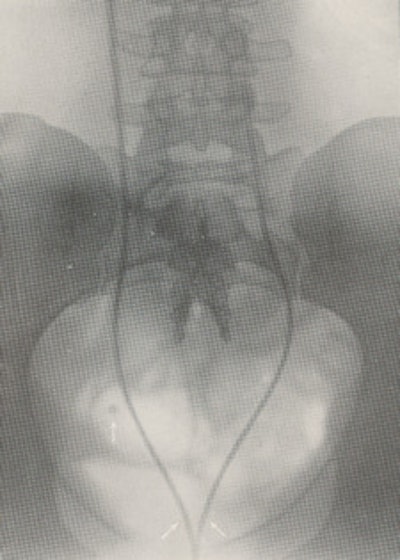

Following the discovery of the x-ray in 1895, Hurry Fenwick was an enthusiastic supporter of the new technique.2 A radiopaque ureteric bougie was passed and a radiograph was made. The position of an opacity in relation to the ureter could be determined with confidence and a phlebolith distinguished from a ureteric calculus (figure 1).

He commented on the distressing situation with the failure of operative surgery when a kidney was opened and damaged to remove a stone when it was no longer in the kidney and was now in the ureter. He estimated that this happened in about 30% of cases when the "x-ray expert" was not called upon to help in the diagnosis. The "x-ray expert" (radiologist) can "guide the urinary surgeon [urologist] with a precision unattainable before the introduction of the [x-ray] method is without cavil."